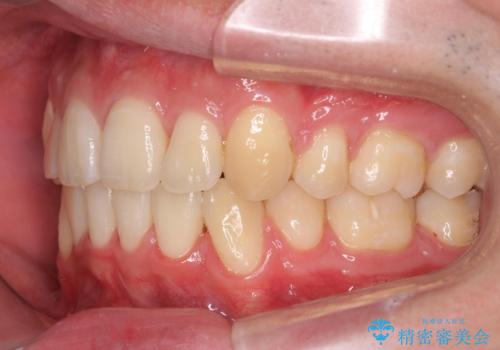

前歯のがたつき 下の八重歯

- 前歯のがたつきを主訴に来院。

上下の前歯の重なりが大きく(過蓋咬合)時間がかかりましたが、しっかり浅く仕上げることができました。